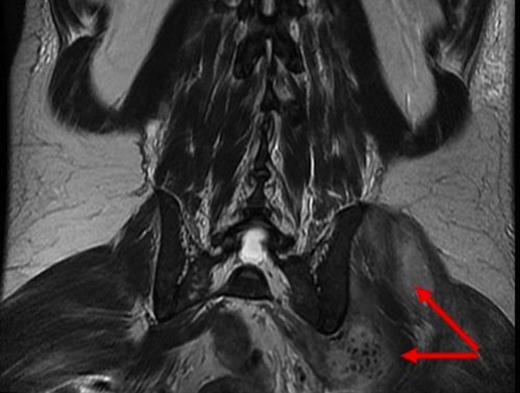

The patient underwent ultrasound guided drainage of 300ml of pus. Due to ongoing clinical concerns regarding the possibility of metallosis, the patient underwent blood sampling for cobalt and chromium levels, and was imaged with MRI. Chromium and cobalt levels returned elevated (117nmol/L and 169nmol/L), and MRI demonstrated the resolving psoas collection but low signal foci around the left hip which could represent metallic debris (figure 4).

coronal MRI demonstrating ongoing collections around the left hip with low signal foci which may represent metallic debris (red arrow)